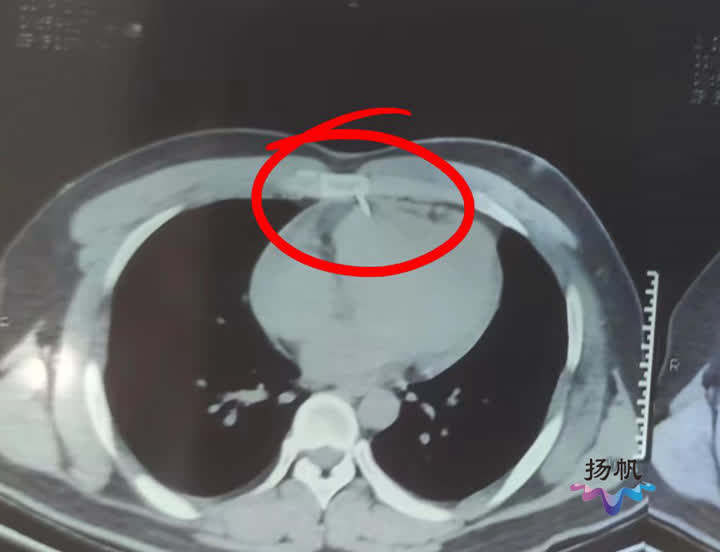

医院心脏大血管病中心主任医师唐程斌介绍,伤者来的时候血压很低心脏里有不少积液,一刻都不能耽搁,他们立即对小伙进行紧急手术。当打开胸腔后医生发现,小伙心脏确实被长钉扎了一个洞,但幸运的是胸骨起到了很好的缓冲作用。原来这根长钉恰巧击中小伙的胸骨,贯穿之后只有约一厘米长扎进心脏。医生感叹小伙子真是命大,如果这根钉子只要偏差一厘米就会贯穿心脏,那么小伙子恐怕当场就没了。